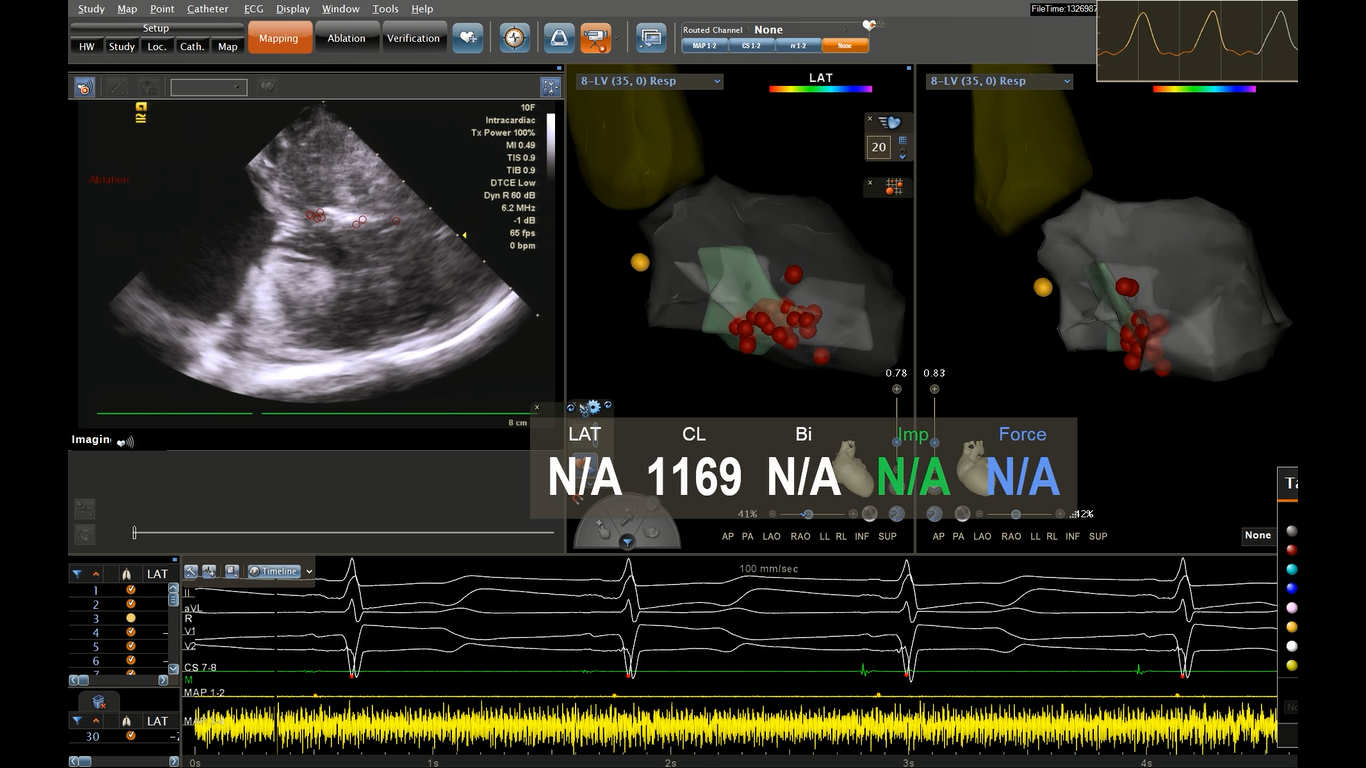

ICE实时监控下行室间隔射频消融